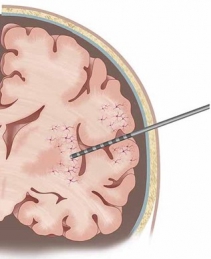

Our research leverages on the rare opportunity of measuring brain activity intracranially in patients affected by pharmaco-resistant epilepsy. In pharmaco-resistant epilepsy patients, neurologists use intracranial electroencephalography (iEEG) to delineate the epileptogenic focus, when non-invasive scalp EEG and other techniques have been insufficient to localize it. iEEG is recorded with intracranial electrodes and it has higher spatial resolution and higher signal-to-noise ratio than scalp EEG.

iEEG is generally more used in mesial temporal lobe epilepsy. Therefore, the clinical intracranial macroelectrodes often record electrophysiology signals from the hippocampus, the entorhinal cortex and the amygdala, which are very important for cognitive processes such as memory. However, other areas, such as the frontal cortex, are also not uncommon implantation targets.

| image credits [1] | image credits [2] |